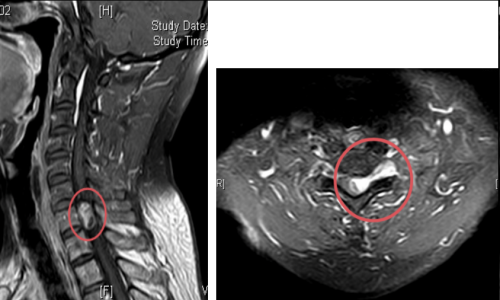

术前核磁检查颈胸段椎管内存在占位性病变,且脊髓已被挤压成线形

脊柱外科一区就诊。医生检查后发现,张淮颈胸段椎管内均存在占位性病变,也就是长了肿瘤!且脊髓已被挤压成线形。